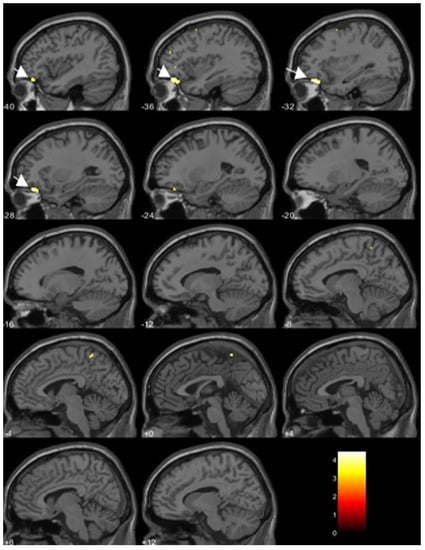

| Dioxin Congeners | Brain Regions | No of Voxels in Each Cluster (k) | Peak Z Scores | MNI Coordinates | ||

|---|---|---|---|---|---|---|

| x | y | z | ||||

| Inverse correlations | ||||||

| TCDD | Anterior temporal cortex | 905 | ||||

| (Left medial temporal pole) | 3.81 | −41 | 20 | −38 | ||

| (Left fusiform gyrus) | 3.90 | −27 | 8 | −47 | ||

| TEQ-PCDDs | Left medial temporal pole | 333 | 3.63 | −39 | 21 | −38 |

| Positive correlations | ||||||

| 1,2,3,4,7,8-HxCDD | Left cerebellum lobule VII | 373 | 3.87 | −42 | −60 | −57 |

| Right middle frontal gyrus | 505 | 3.86 | 41 | 6 | 60 | |